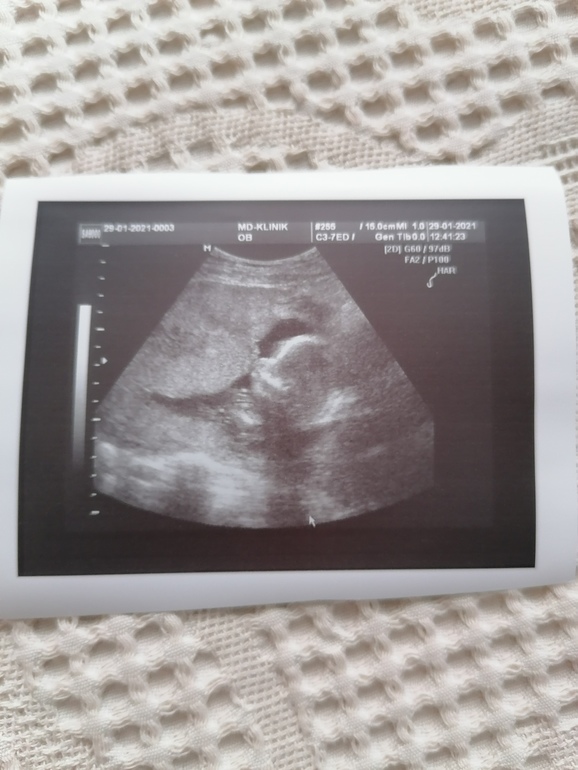

А сыночек молодец, растёт колобочек🙈 вот уж не зря с самого первого теста так его зову😂.

Сегодня нам 17.3 по месячным, а сынок на 18-19 недель весит 271 гр. 🙏🙏🙏👶, сердечко 140 ударов

Фоточка так себе сегодня, потому, что основное узи было на шейку, а его пару минут померила и все.